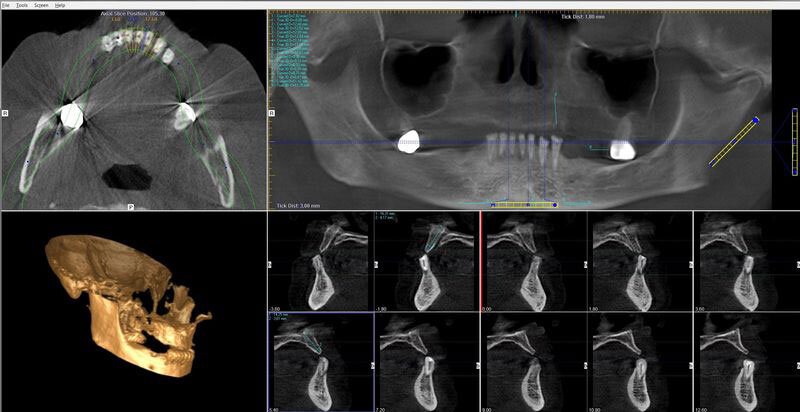

Zubní CT

Pro zhodnocení celkového stavu chrupu je na klinice k dispozici OPG rtg, který umožní upřesnění diagnostiky i naplánování celkového léčebného plánu

Jejich součástí je i intraorální rtg, který umožňuje zhotovení rtg snímku přímo na křesle i během ošetření.

Dávka záření je díky nejnovějším technologiím zcela minimální.